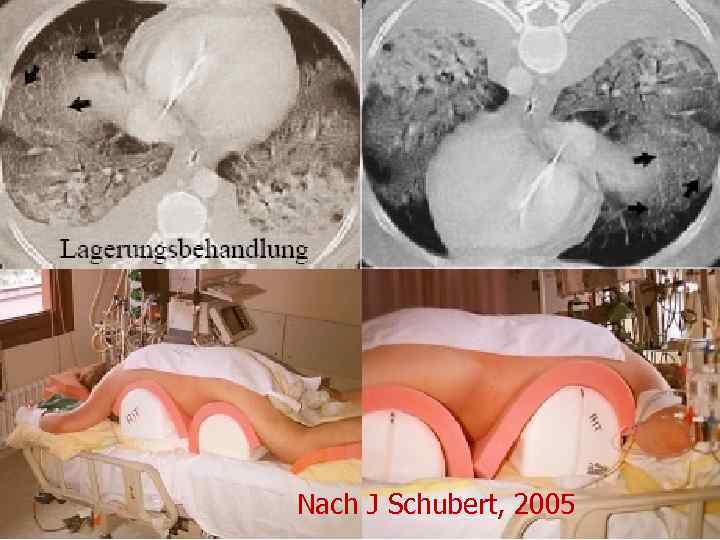

Nach J Schubert, 2005

Nach J Schubert, 2005